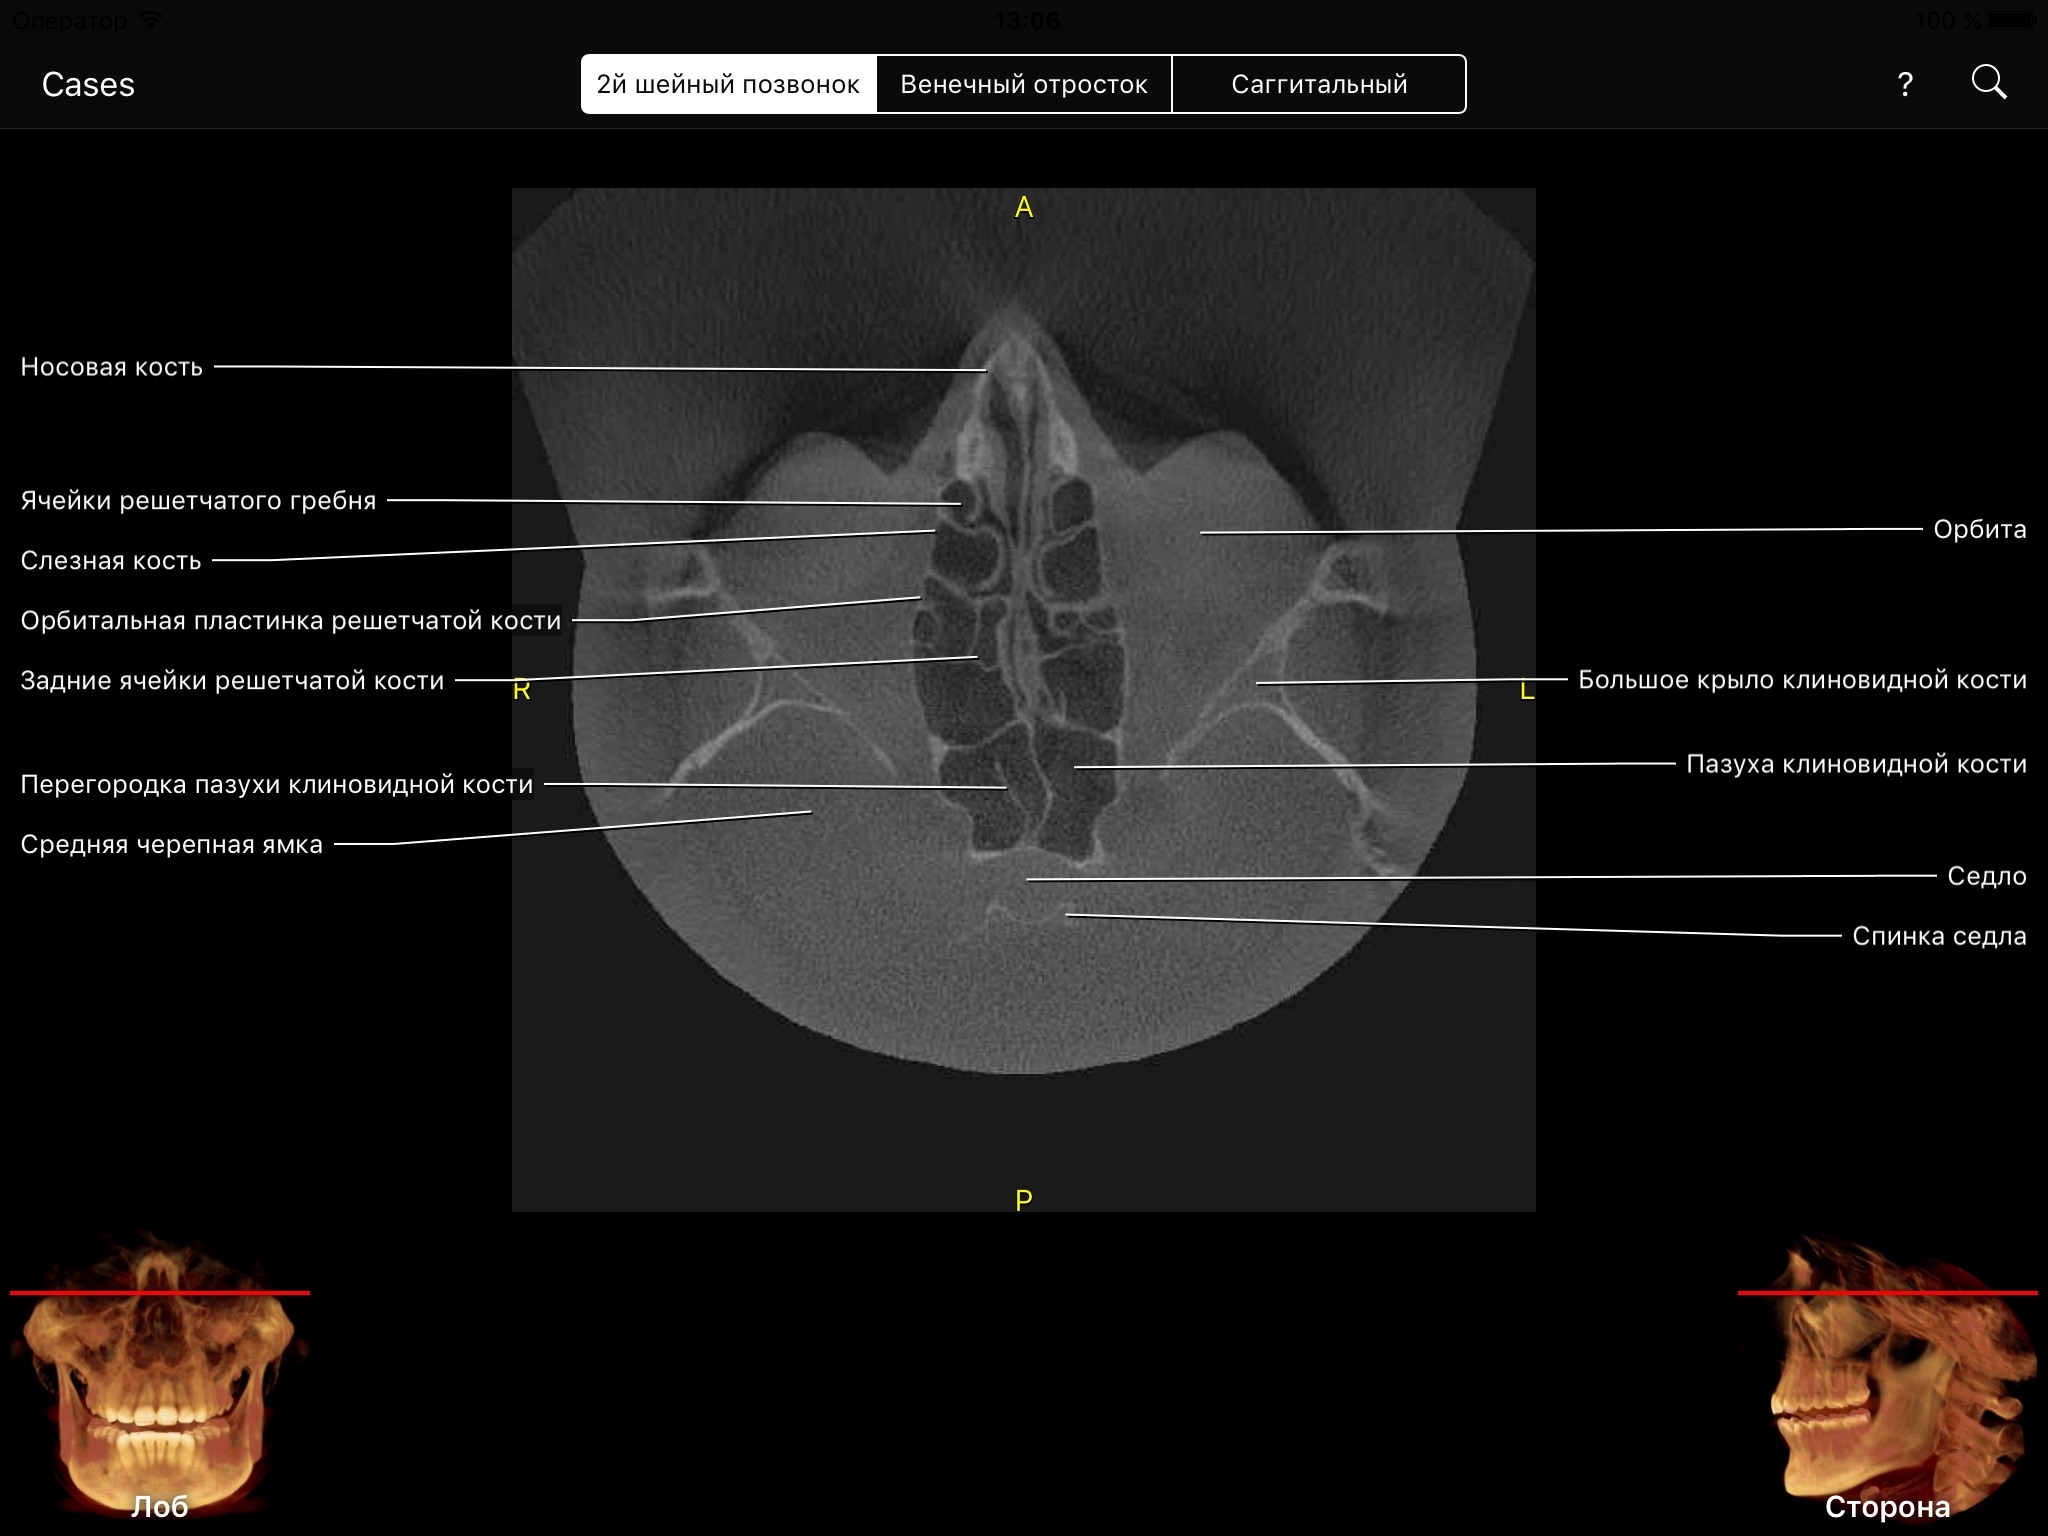

Cone Beam CT has revolutionized diagnosis and treatment planning. Clinicians can use a Cone Beam CT volume to view patient’s head in 3 dimensions using multi-planar reformatted views (MPR), known as: axial, coronal, and sagittal. The volumetric data set has no magnification and no superimposition.

CBCT app allows clinicians, residents, and dental students to learn anatomical landmarks as if they were looking at a CBCT data set through the CBCT viewing software but with all the landmarks visible and animated through all MPR views.

The level of interactivity and visualization is unprecedented. This amazing app covers hundreds of anatomical landmarks visible on CBCT data sets from small to medium to large field of views (FOVs). It also allows you to test your knowledge through the quiz mode, which is very cool. You can also search for a landmark or pick it up from an alphabetical list and the app fly you there.